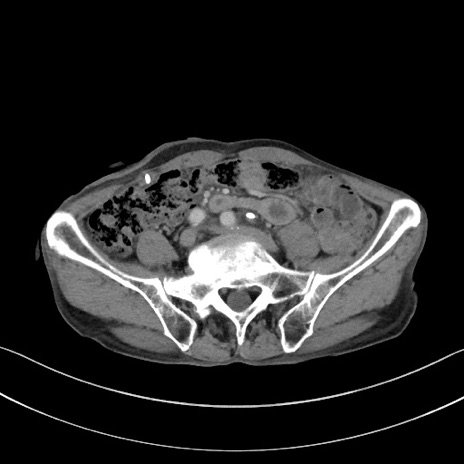

症例3(横断像)

【症例】 70歳代男性

【主訴】右鼠径部腫瘤、疼痛

【現病歴】本日朝より上記主訴あり、受診。

【既往歴】膀胱癌にて膀胱全摘、両側尿管皮膚瘻

【データ】WBC 5600、CRP 0.56